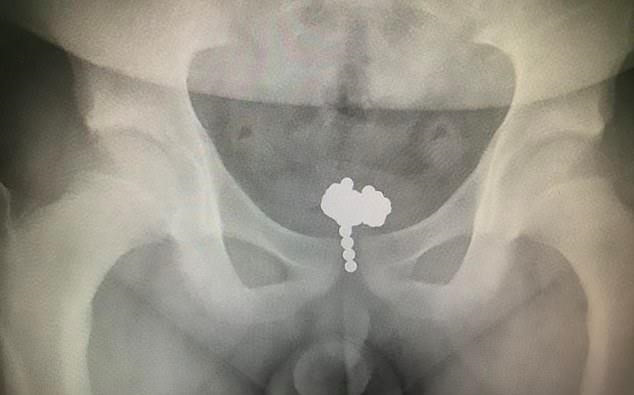

Bác sĩ Tao Chang tại Bệnh viện Nhi thuộc Đại học Y khoa Chiết Giang cho biết kết quả chụp X-quang cho thấy mỗi viên bi có đường kính 5 mm, bó lại với nhau trong bàng quang sau khi cậu bé đẩy chúng lên qua đường tiết niệu.

| Hình ảnh X-quang cho thấy những viên bi nam châm cuộn vào nhau ở bên trong bàng quang. Ảnh: Dailymail. |